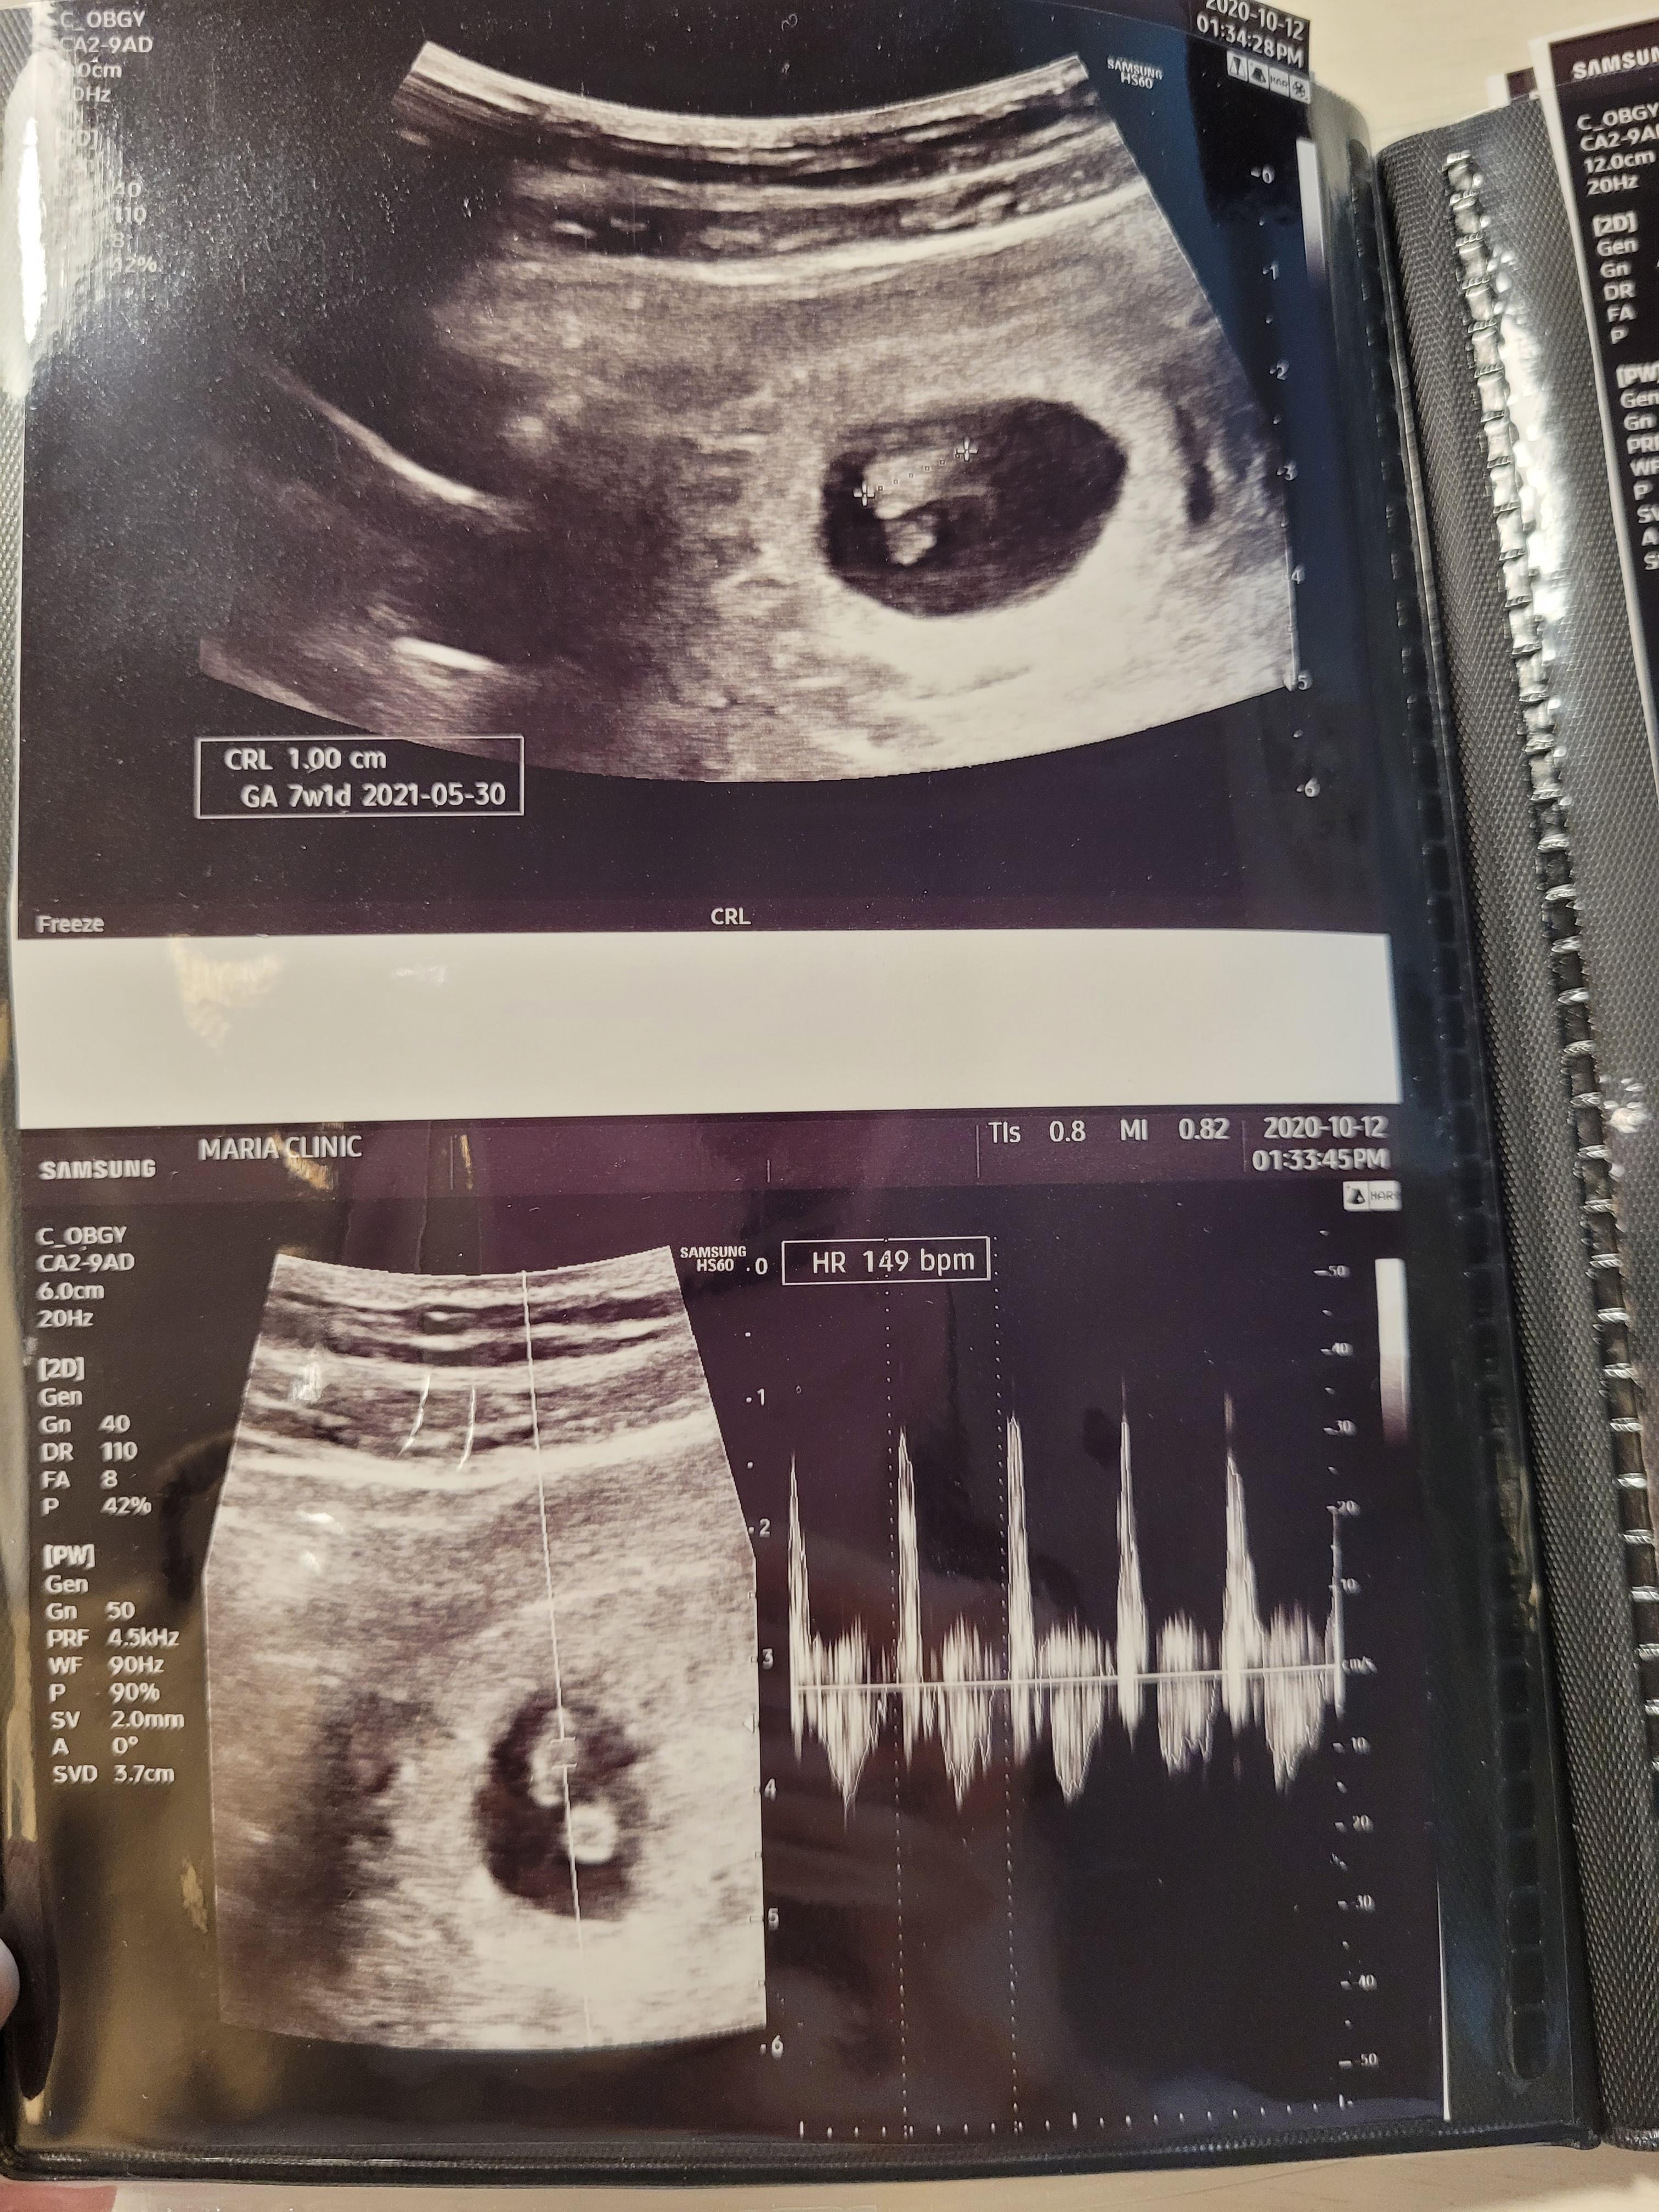

임신 7주 0일 / 심장소리 확인

7주차에는 심장소리를 들을 수 있는 주수에요.

병원마다 좀더 일찍 들려주기도하던데, 저는 딱 7주차에 확인할 수 있었어요.

아기는 1cm정도 였고, 심장박동수도 주수에 맞게 잘 뛰더라고요^^